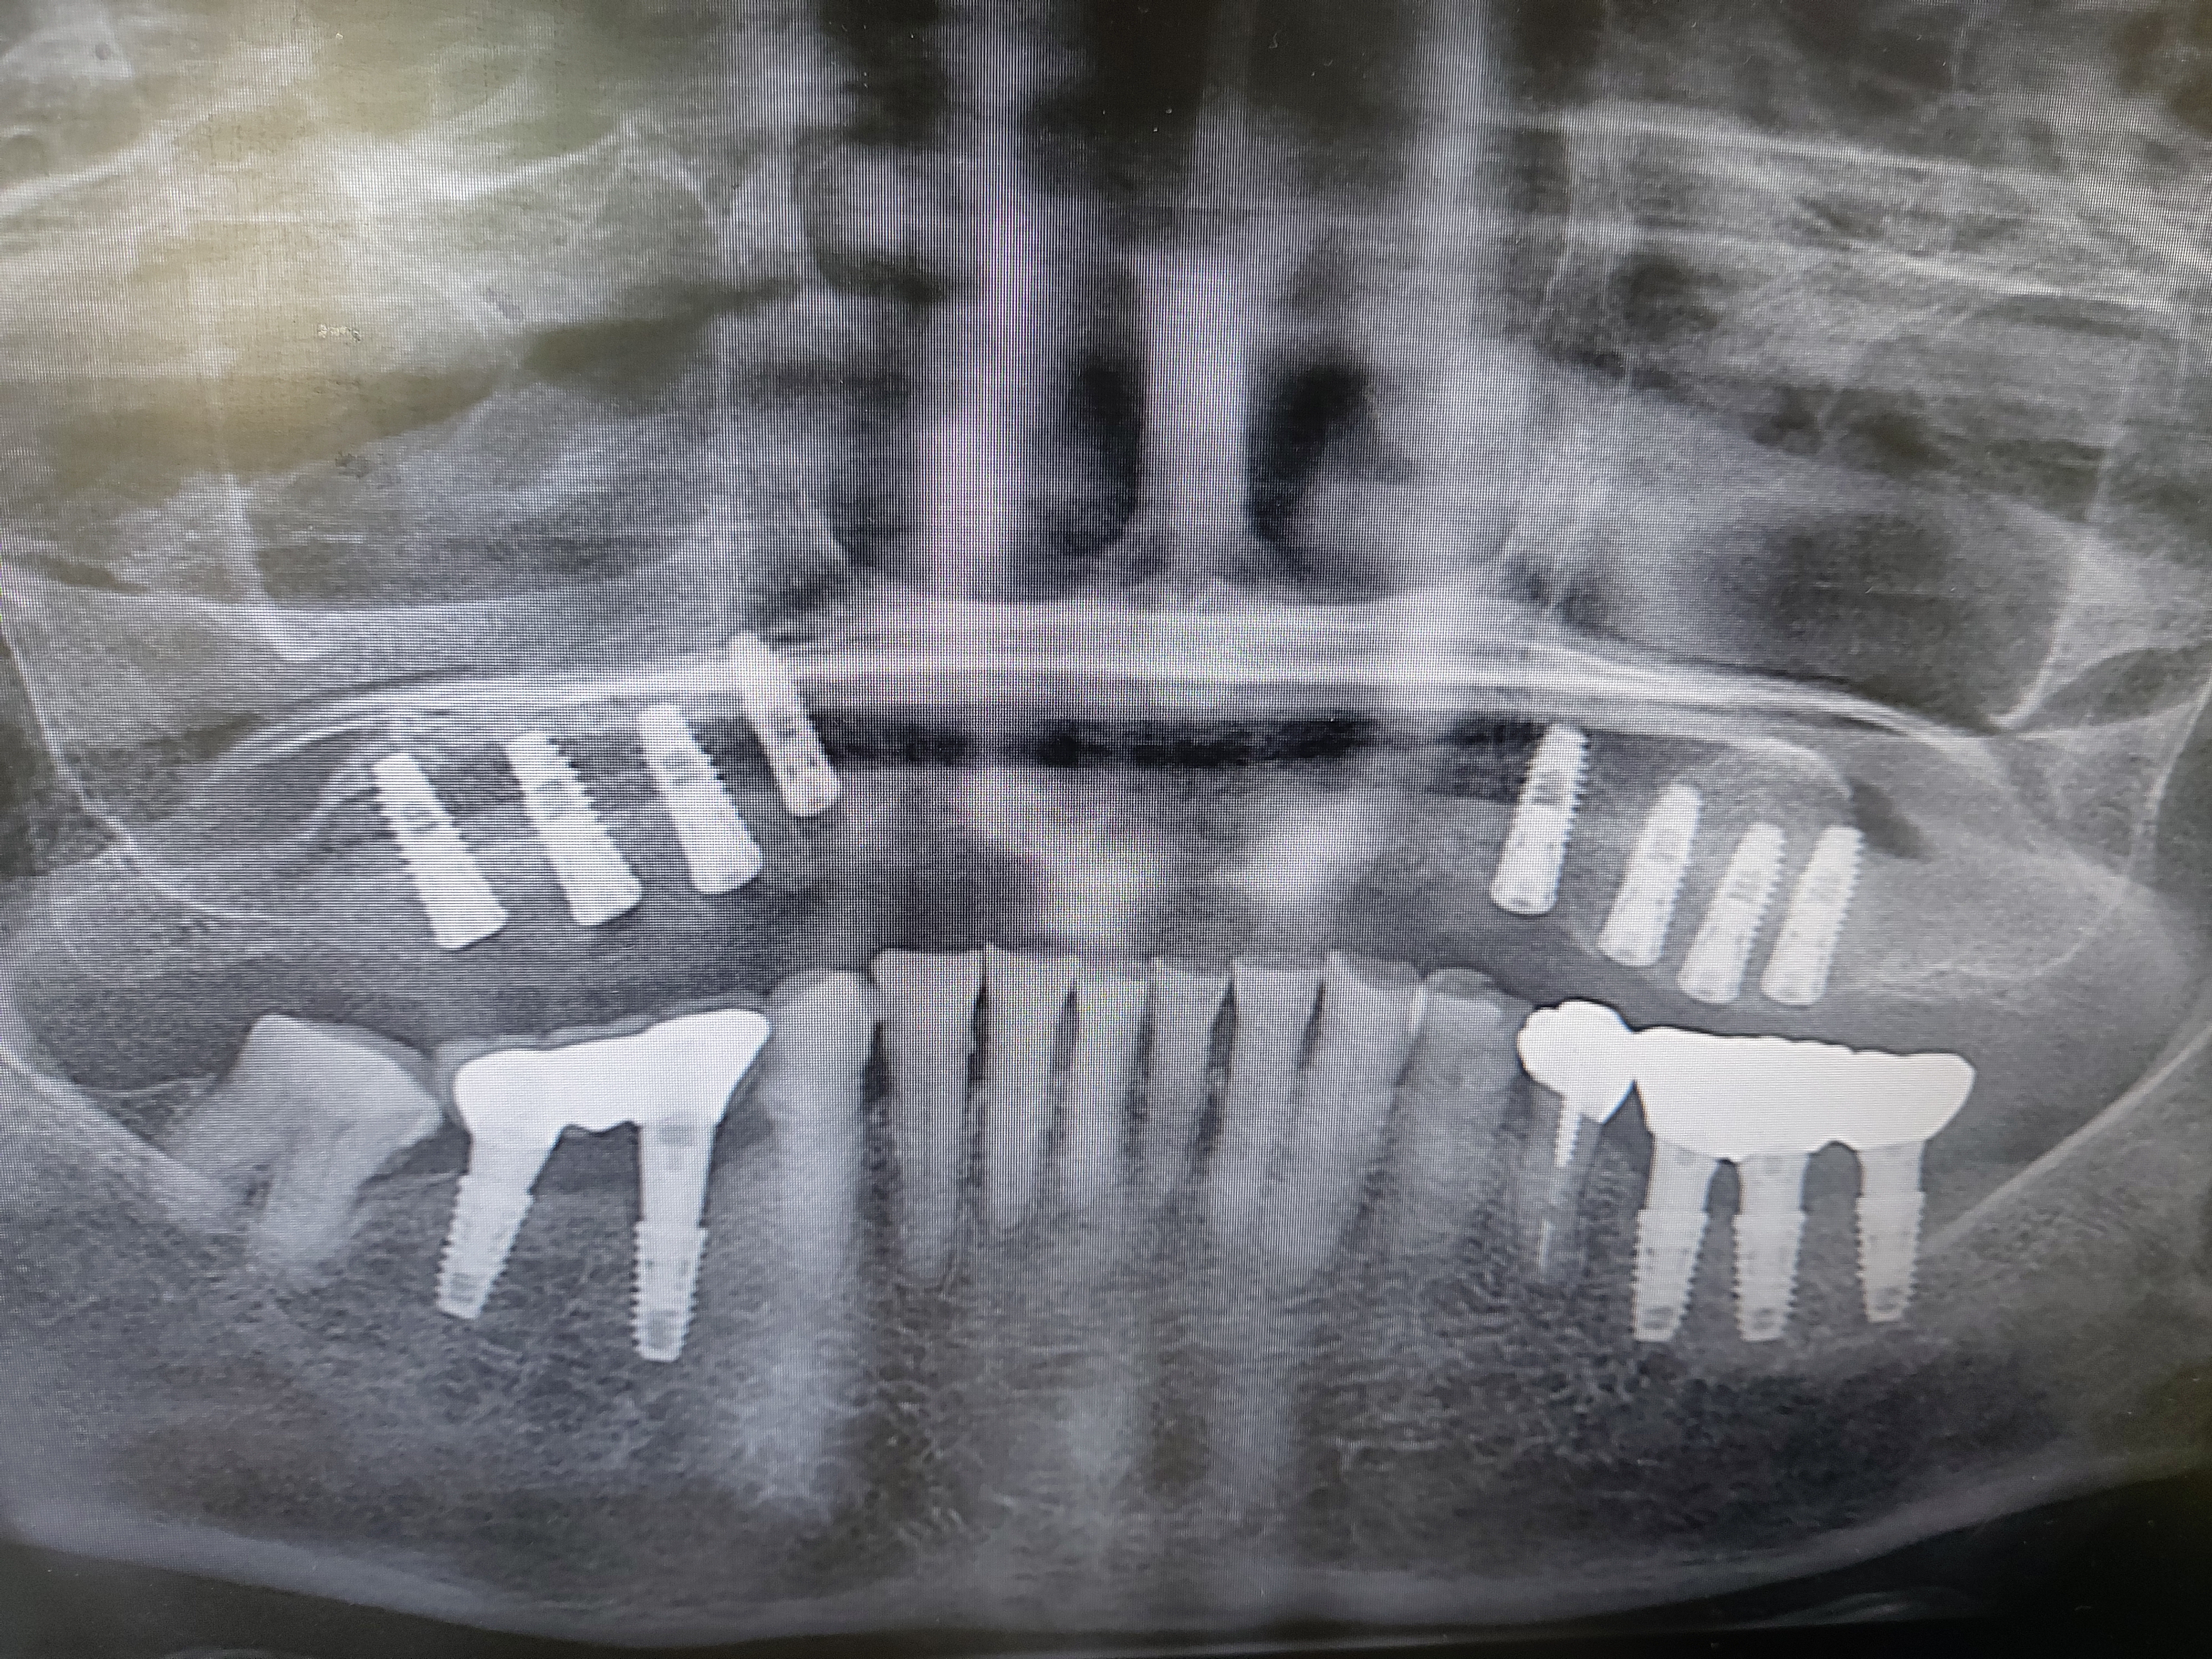

상악동이 아랫쪽으로 내려오면 치조골의 높이가 부족해집니다. 임플란트를 식립할 만큼의 뼈가 부족해지기 때문에 내려앉은 상악동의 점막을 들어올려서 그 공간속에 뼈를 넣는 다음

임플란트를 식립하게 됩니다.

기본적으로 임플란트를 식립할 경우 최소 8~ 10 mm정도의 뼈가 필요하며 잔존골의 높이에다가 부족한 만큼 뼈를 이식하게 됩니다.

통상적으로 수술 후 보철 완성시 까지는 6개월 전후이며 잔존골이 부족한 경우에는 조금더 시간이 걸리기도 합니다.